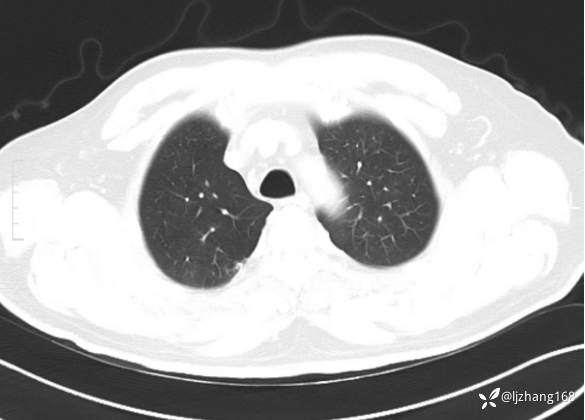

中年男患,右肺团片影,炎症0R肿瘤?

患者年龄:47岁

主诉:咳嗽、 咳痰伴气短20+天

简要病史: 20+天前患者因受凉后出现阵发性咳嗽,咳少量白色粘痰,痰易咳出,伴活动后气短,伴纳差、乏力、全身酸痛,伴多汗,无痰中带血及咯血,无发热、畏寒及寒战,无潮热、盗汗,无夜间阵发性呼吸困难及端坐呼吸,无声嘶,无头晕、头痛,无黑矇、晕厥及意识障碍,无腹痛、呕血及黑便等不适,遂就诊于当地医院予以输液等治疗后未见明显好转(具体诊疗不详),现为进一步诊治就诊于我院门诊,以“右肺占位”收入我科。病来饮食欠佳,近期体重下降(具体不详)。既往糖尿病病史7+年,未规律监测血糖,血糖控制不佳。否认“高血压、冠心病及慢性肾脏病”等慢性疾病史。否认“肝炎、结核、伤寒”等传染病史。否认食物、药物过敏史。否认外伤、输血史,预防接种史不详。

辅助检查:糖化血红蛋白12.3%。肺炎支原体IgG、IgM、呼吸道合胞病毒均未见明显异常。胸部CT:右肺上叶阻塞性肺炎。